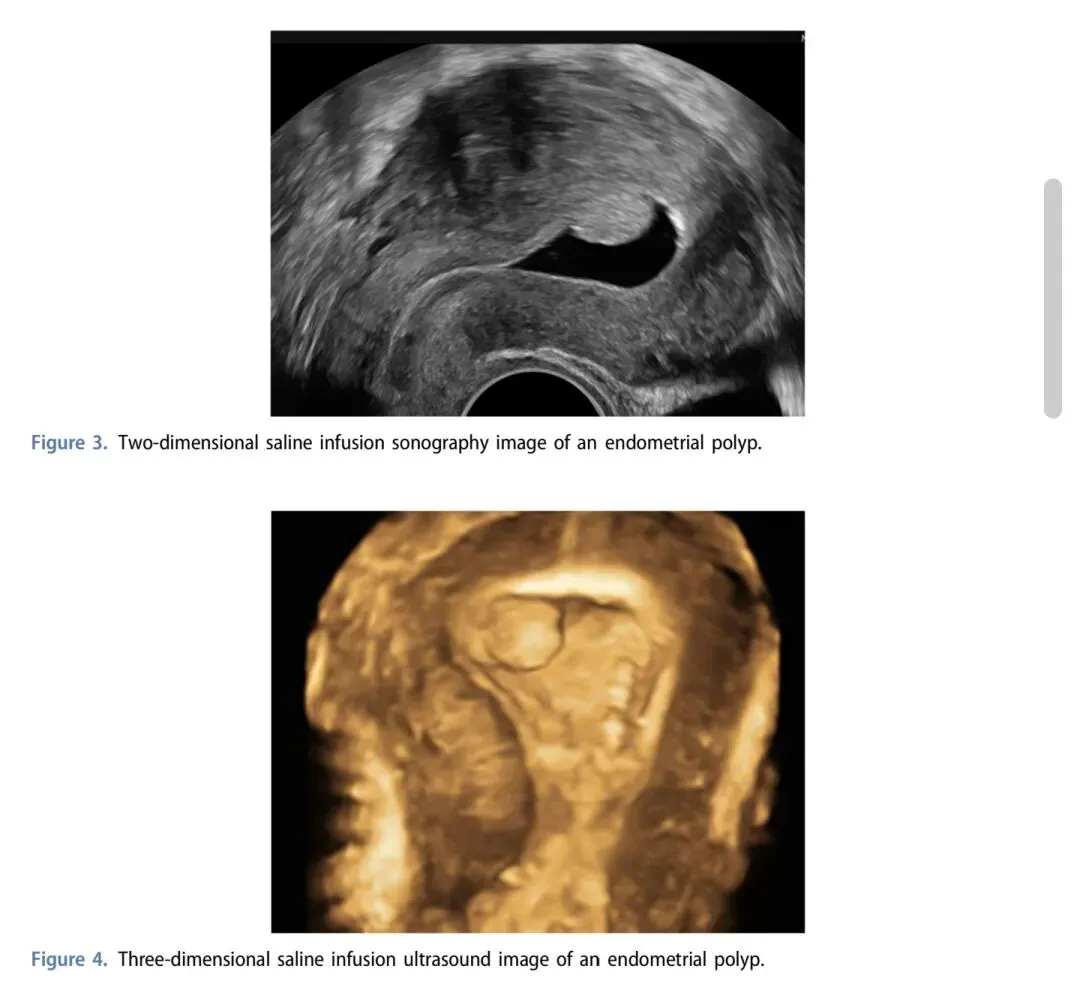

2. 3D超声:对2D疑似病例有确诊价值,依赖操作者经验

3. 生理盐水灌注超声(SIS):敏感度92.0%、特异度93.0%,准确率接近宫腔镜;可同时评估宫腔粘连、输卵管通畅度